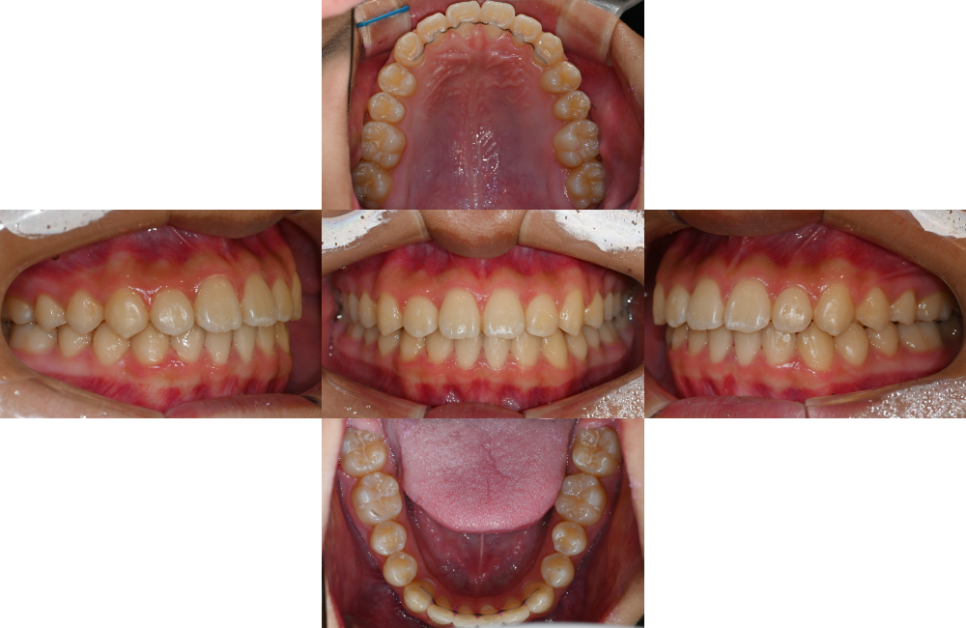

2025.01.24

치열이 개선되면

여러 가지 긍정적인 변화를

경험할 수 있습니다.

우선 구강 위생 관리가 훨씬 쉬워집니다.

엇갈려 있던 치열이 펴지면서

칫솔질이 자연스럽게 편해지고,

음식 찌꺼기가 끼는 일도

줄어들게 되는데요.

이는 충치나 치주 질환의 확률을

크게 줄여주는 효과를 가져다 줍니다.

또한 턱관절의 통증을 줄여주거나

안면 비대칭을 개선하는 등

배열 개선 외에도 여러 문제들을

해결할 수 있는 치료 방법이랍니다.

치료기간 : 23.08.17 ~2025.01.24